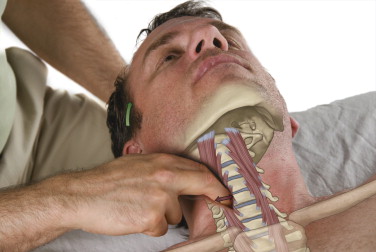

Rintanarsi nel proprio mondo virtuale diventa allora una vera postura, diventata una vera e propria sindrome: “Text Neck” o “cervicalgia da smartphone ” .

Con questo nome si identifica una sindrome dovuta ad un’errata postura nell’uso di apparecchi elettronici, che causa dolore e infiammazione a carico del collo, delle spalle, delle zone cervicale e toracica della colonna vertebrale, ipertrofia ed ipotrofia dei muscoli del collo, fino a modifica delle curve vertebrali, scompensi posturali e disfunzioni neurologiche.

La postura che, spesso, si assume nel guardare gli schermi di tablet, telefoni e computer porta la testa fuori dal suo asse naturale per molto tempo, andando a caricare le strutture con un peso fino a 5 volte maggiore del carico ordinario : la testa in posizione naturale pesa circa 5kg, inclinata di 60° arriva a pesarne 27.

Questo aspetto del coinvolgimento a distanza e indiretto è intrinseco nel trattamento Shiatsu, qualsiasi stile si pratichi.

Da un punto di vista legato alla medicina tradizionale cinese, la cervicalgia da smartphone interessa principalmente il percorso dei meridiani di Vescica e Stomaco e i loro corrispettivi meridiani tendino-muscolari. C’è poi un aspetto legato al movimento Legno, che governa muscoli e tendini, e quindi i meridiani di Fegato e Vescica Biliare. Nei singoli casi, potrà esserci un coinvolgimento dei meridiani correlati : Intesino Tenue, Intestino Crasso, Polmone, Ministro del Cuore.

Il meridiano di Vescica, con il suo importante compito di tenere la “retta via” e la corretta postura risulta fondamentale. Nel trattamento si porrà attenzione alla zona cervicale: il cardine per “cambiare punto di vista” e quindi poter cambiare direzione.

Il meridiano di Stomaco è legato alla posizione “centrata”, quindi forte è il legame con il baricentro del corpo : l’addome ed il bacino. Il trattamento della parte finale del meridiano dal ginocchio al piede, coinvolge punti, come ST38, legati al trattamento delle spalle.

Questo collegamento tra la zona tibiale e le spalle risulta più facilmente comprensibile attraverso il bilanciamento reso famoso dal Dr. Richard Tan, che ha ripreso e sintetizzato quanto presente nella tradizione: una visione del corpo in cui braccia e gambe sono un riflesso del tronco.